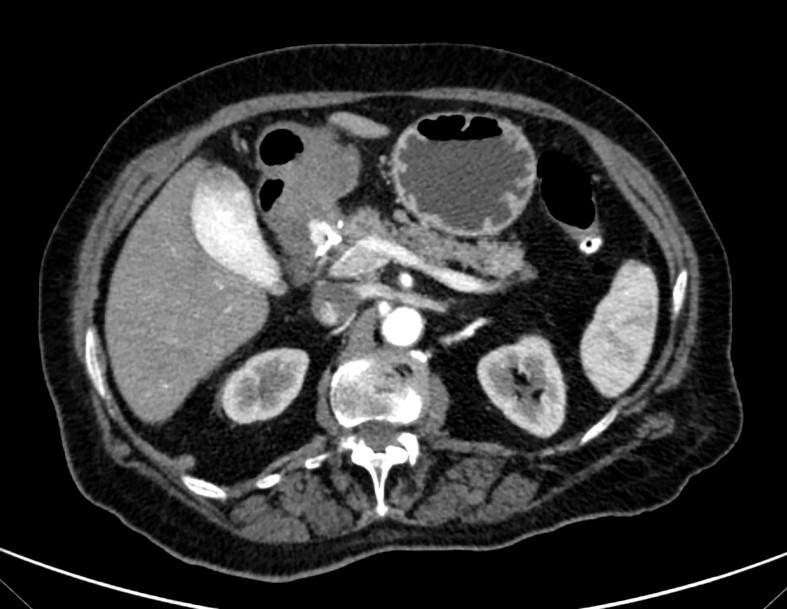

PRESENTATION OF CASE

We report the case of an 82-years-old female presenting with abdominal pain and hematemesis. Upper gastrointestinal endoscopy retrieved a large duodenal mass and subsequent CT scans identified a large GAA with contrast extravasation. Endovascular procedure included selective arteriography, microcatheterization, and embolization.

我们报告了一例82岁女性,表现为腹痛和呕血。上消化道内镜检查发现十二指肠有一个大肿块,随后的CT扫描确定为一个大的GAA并伴有造影剂外渗。血管内治疗包括选择性动脉造影、微导管插入和栓塞。